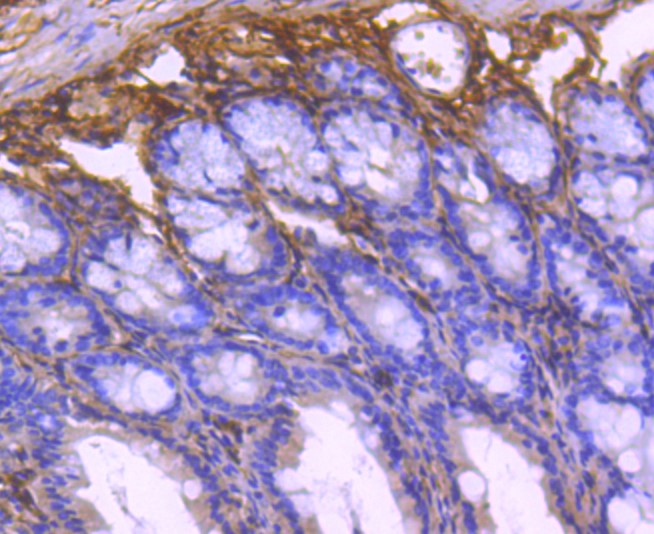

ApplicationsImmunoFluorescence, Western Blot, ImmunoCytoChemistry, ImmunoHistoChemistry, ImmunoHistoChemistry Paraffin

- Delivery Days Customer16

- ApplicationsImmunoFluorescence, Western Blot, ImmunoCytoChemistry, ImmunoHistoChemistry, ImmunoHistoChemistry Paraffin

- Applications SupplierWB(1:300-5000), IHC-P(1:200-400), IF(ICC)(1:50-200), IHC()